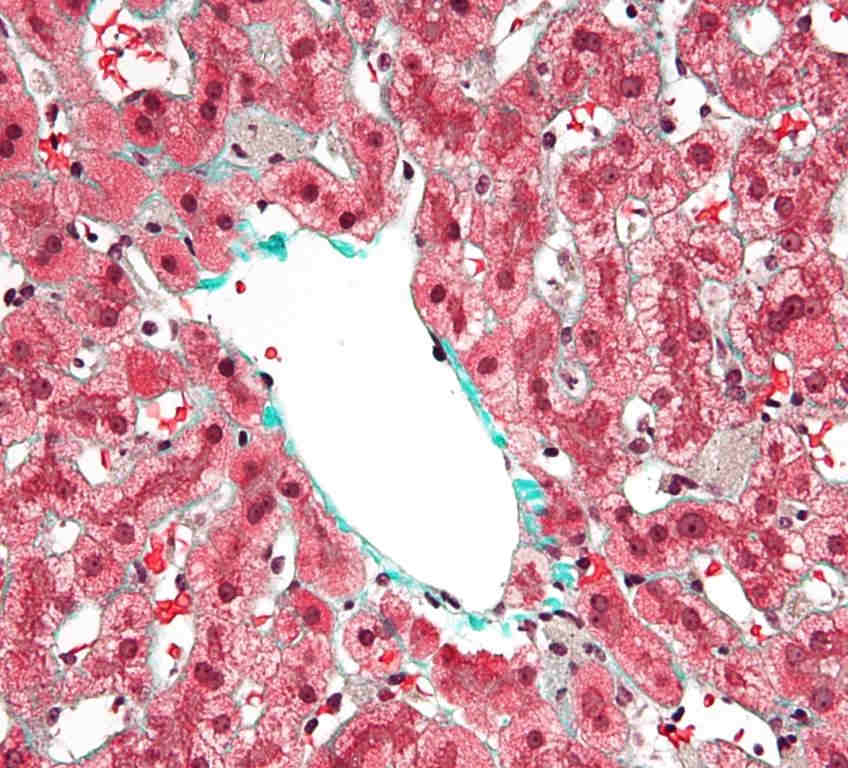

Локализация клеток Купфера в печеночной архитектуре

Печень представляет собой сложный орган, состоящий из ряда высокоспециализированных типов клеток, которые распределены внутри синусоидальной структуры печени. Гепатоциты, которые составляют основную массу печени, считаются рабочими лошадками и выполняют широкий спектр метаболических, регуляторных и токсикологических функций. Печеночная синусоида выстилается специализированными печеночными синусоидальными эндотелиальными клетками, характеризующимися наличием фенестр (окон). Внутри синусоиды находятся клетки Купфера, а также другие клетки врожденной иммунной системы, включая естественные киллеры, естественные киллеры-Т-клетки и дендритные клетки. Близость клеток Купфера к паренхиматозным и непаренхиматозным клеткам печени поддерживает способность клеток Купфера регулировать функцию печени, как в здоровом состоянии, так и в болезни. В здоровой печени клетка Купфера демонстрирует то, что было названо «толерогенным» фенотипом. Эта толерантность необходима для предотвращения нежелательных иммунных реакций в отношении входящих в печеночную синусоиду иммунореактивных веществ, включая материалы, полученные из кишечника, а также антигены, присутствующие в мертвых или умирающих клетках, поскольку в печени они удаляются из кровообращения.